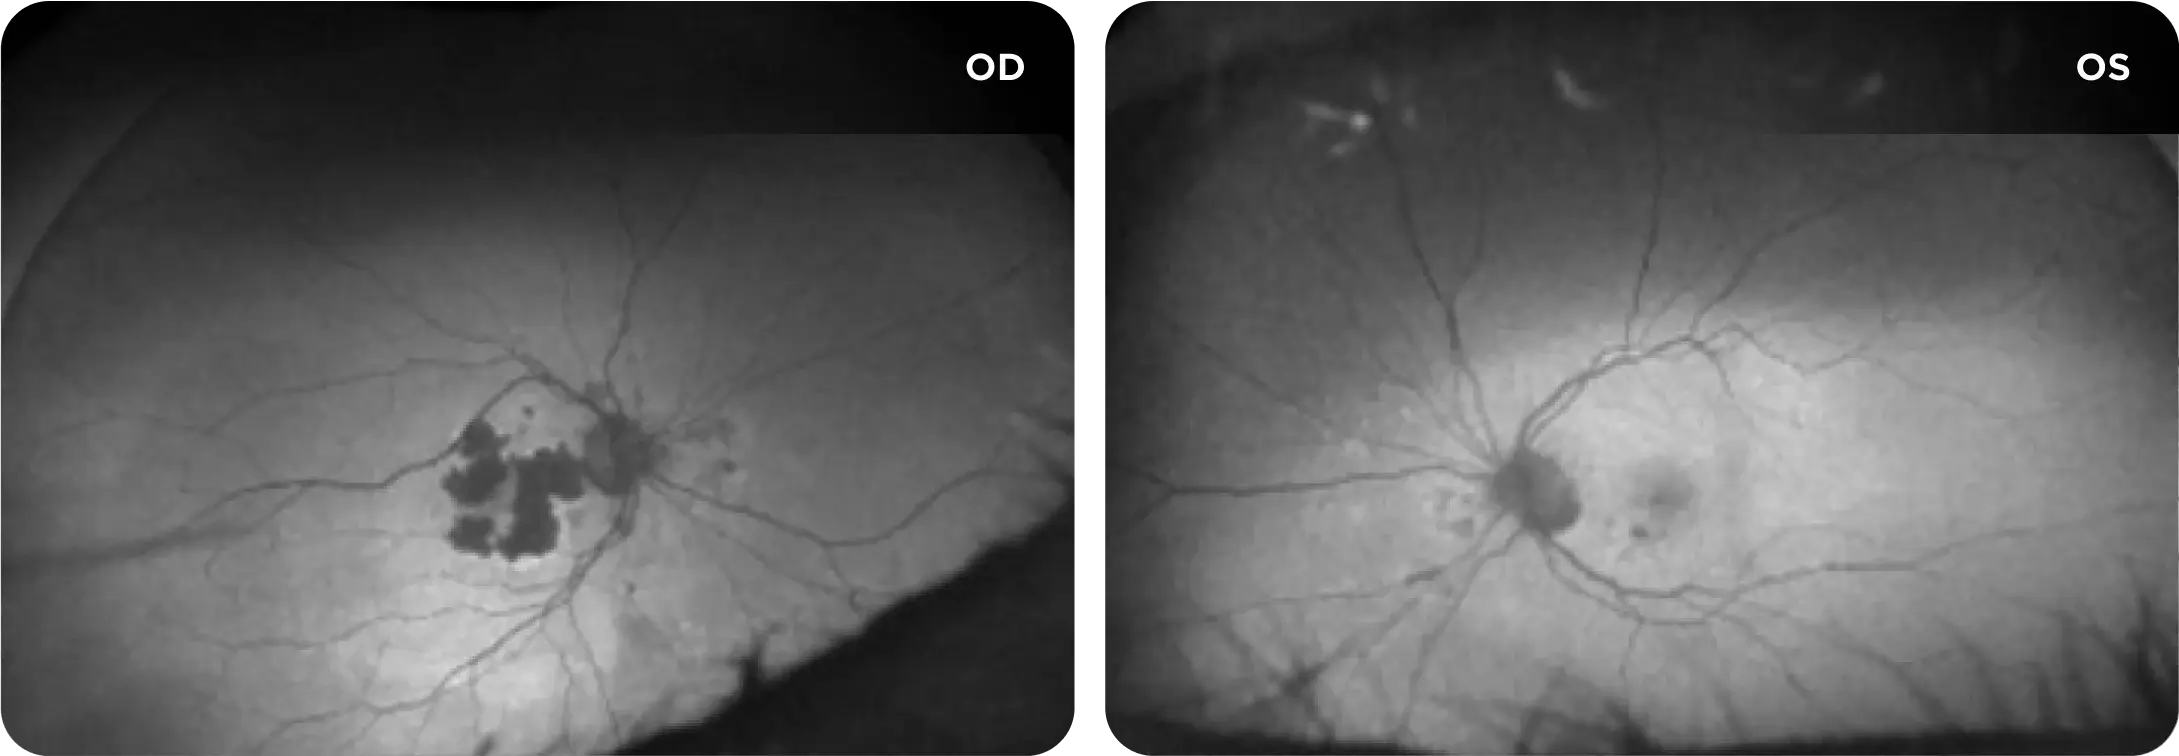

Neovascular AMD

- In clinical trials, use of IZERVAY was associated with increased rates of neovascular (wet) AMD or choroidal neovascularization (7% when administered monthly and 4% in the sham group) by Month 12. Over 24 months, the rate of neovascular (wet) AMD or choroidal neovascularization in the GATHER2 trial was 12% in the IZERVAY group and 9% in the sham group. Patients receiving IZERVAY should be monitored for signs of neovascular AMD.

IZERVAY™ (avacincaptad pegol intravitreal solution) is indicated for the treatment of geographic atrophy (GA) secondary to age-related macular degeneration (AMD)